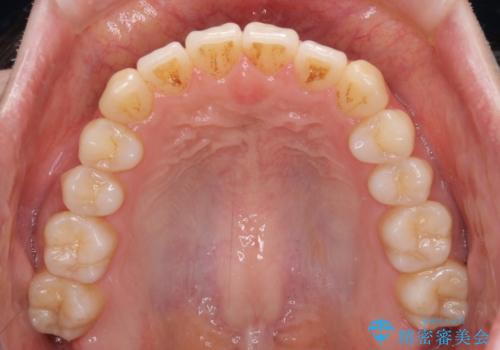

オープンバイトでかみにくい インビザラインによる矯正治療

- 前歯の上下スペースによる食べにくさを気にして来院された患者様です。

インビザラインにより上下の前歯の隙間を閉じていくこととしました。

上下の奥歯を圧下させるようにすることで、前歯を接触させるように計画しました。

上下の隙間に舌が入り込むことがオープンバイトの原因であったため、舌の筋肉のトレーニングも並行して行い、後戻りの抑制を図りました。